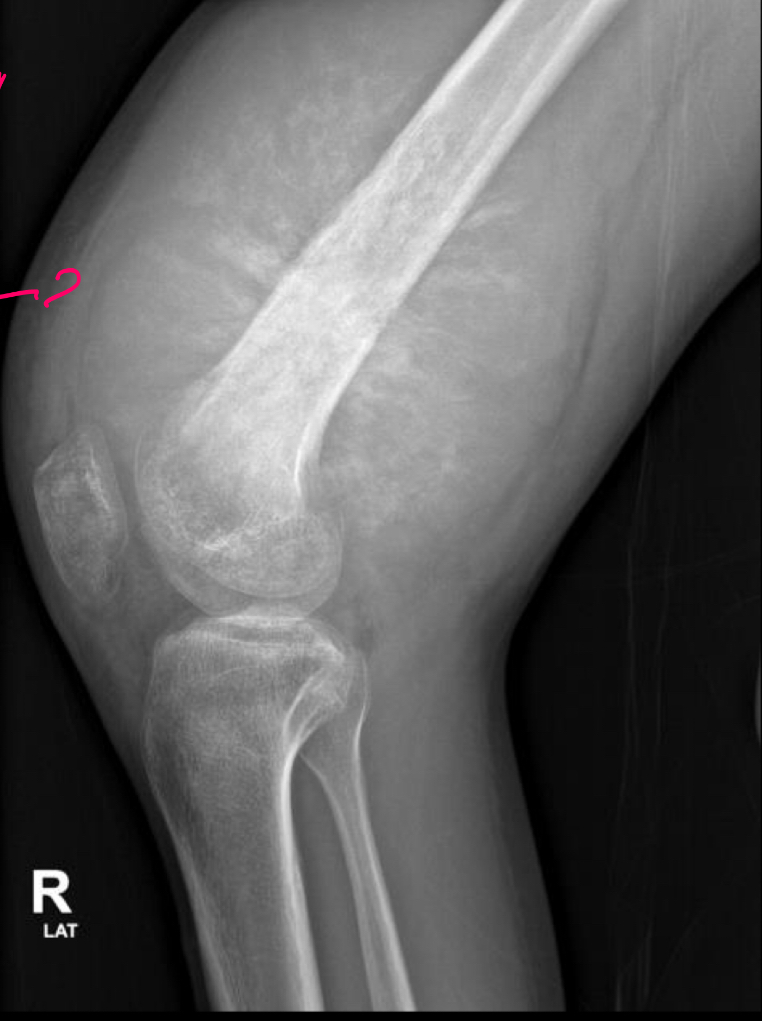

Q

Q podemos ver

A

rayos de sol: reac periostica

13

Q tiene

Osteosarcoma y FX en condilo lat